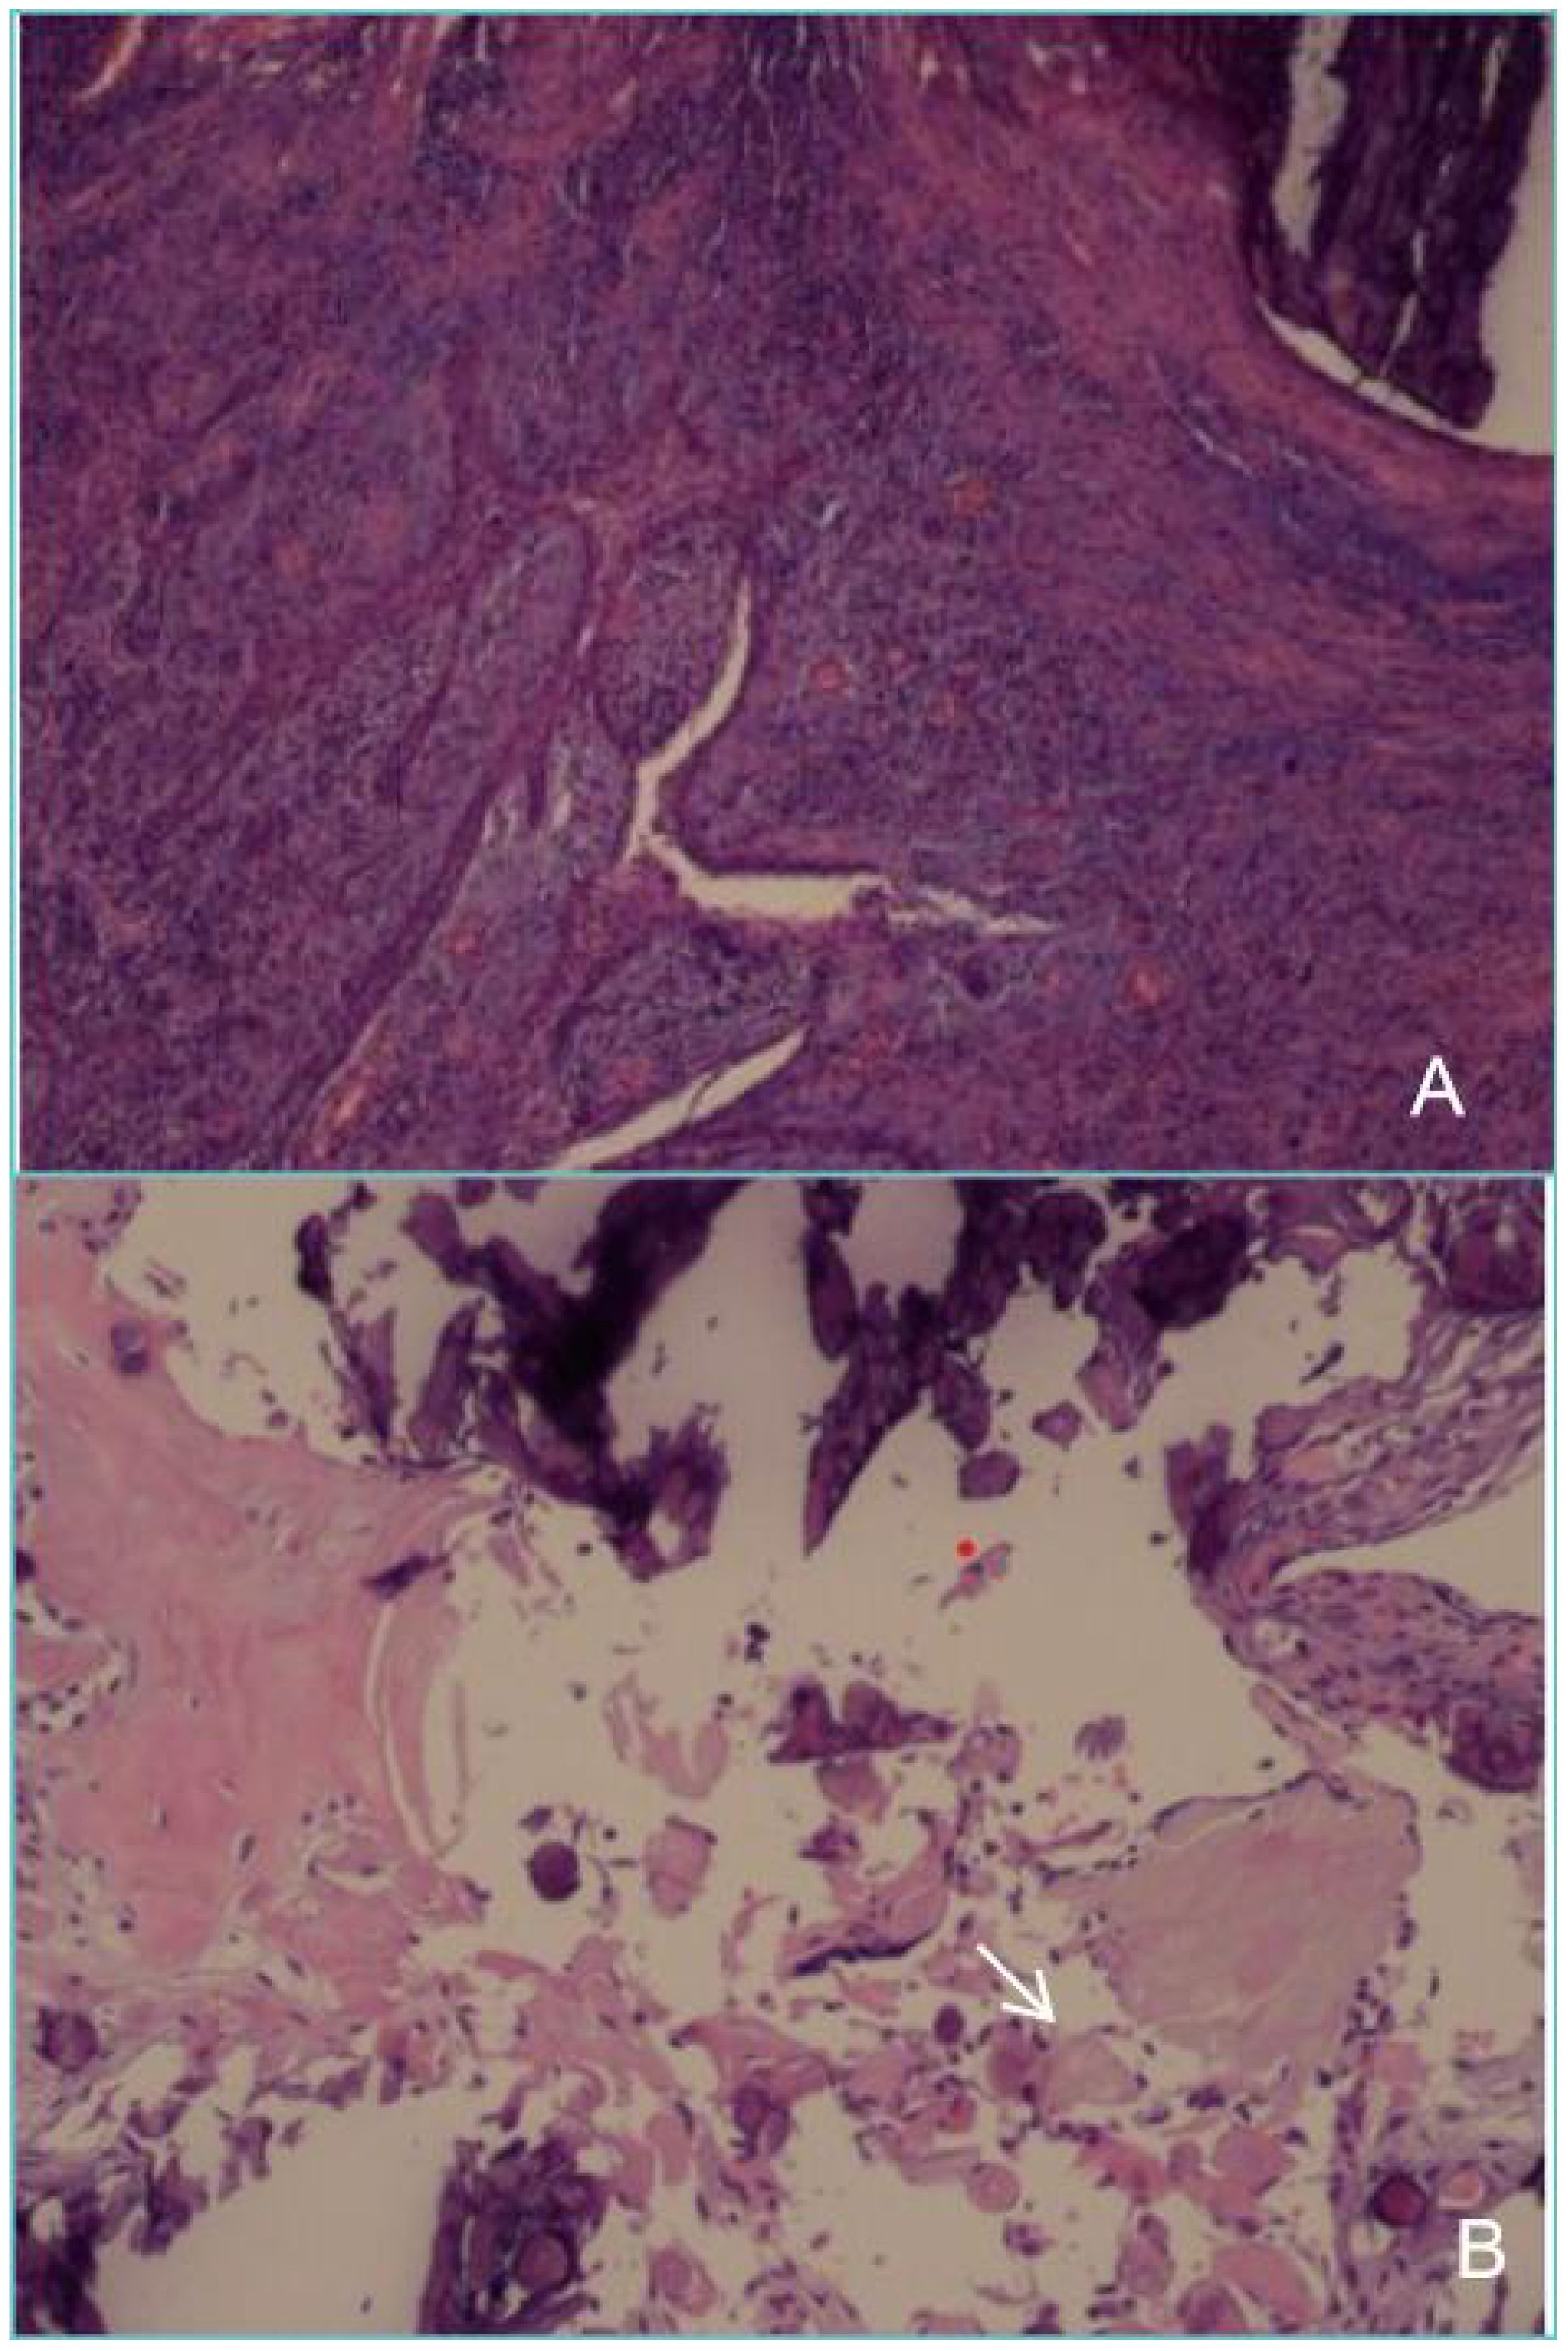

Dentinogenic ghost cell tumor (DGCT) is a rare odontogenic neoplasm that presents with nonspecific clinical manifestations and imaging features. It is more prevalent in elderly patients, with cases in children being extremely rare. This article presents a case study of a 10-year-old male patient who exhibited symptoms of swelling and pain in the left cheek for a duration of two weeks. Cone beam computed tomography (CBCT) demonstrated a hypodense lesion involving the left maxilla, with extension into the maxillary sinus and buccal cortical expansion. The patient underwent decompression, and histopathological examination of the intraoperative specimen suggested a diagnosis of calcifying odontogenic cyst (COC). One year after decompression, the patient underwent a tumor resection and the diagnosis of DGCT was confirmed by the post-operative pathology. Six months after tumor resection, CBCT showed complete bone remodelling in the lesion area. The patient is currently undergoing regular follow-up. This case provides an important reference for the diagnosis and treatment of pediatric DGCT, helping clinicians to develop individualised treatment plans.